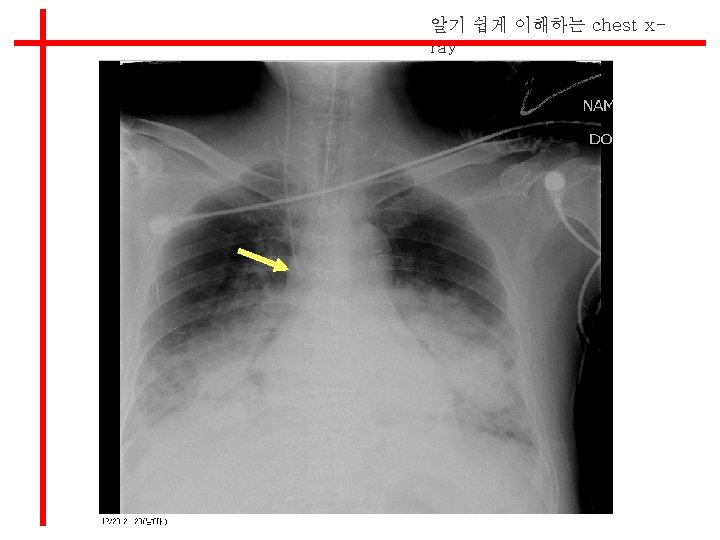

알기 쉽게 이해하는 chest xray l Position of Tubes and Catheters

알기 쉽게 이해하는 chest xray E-tube가 Rt main bronchus에 들어감 E-tube 재고정함

알기 쉽게 이해하는 chest xray Central venous catheter l tip이 SCV나 innominate vein내에 위 치한다. l x-ray상 Rt bronchus 상단이고, Aortic arch에 위치한다.

알기 쉽게 이해하는 chest xray Side hole